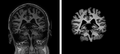

OASIS brain with skull

Skull.png

OASIS brain skull-stripped

Ss volume.png